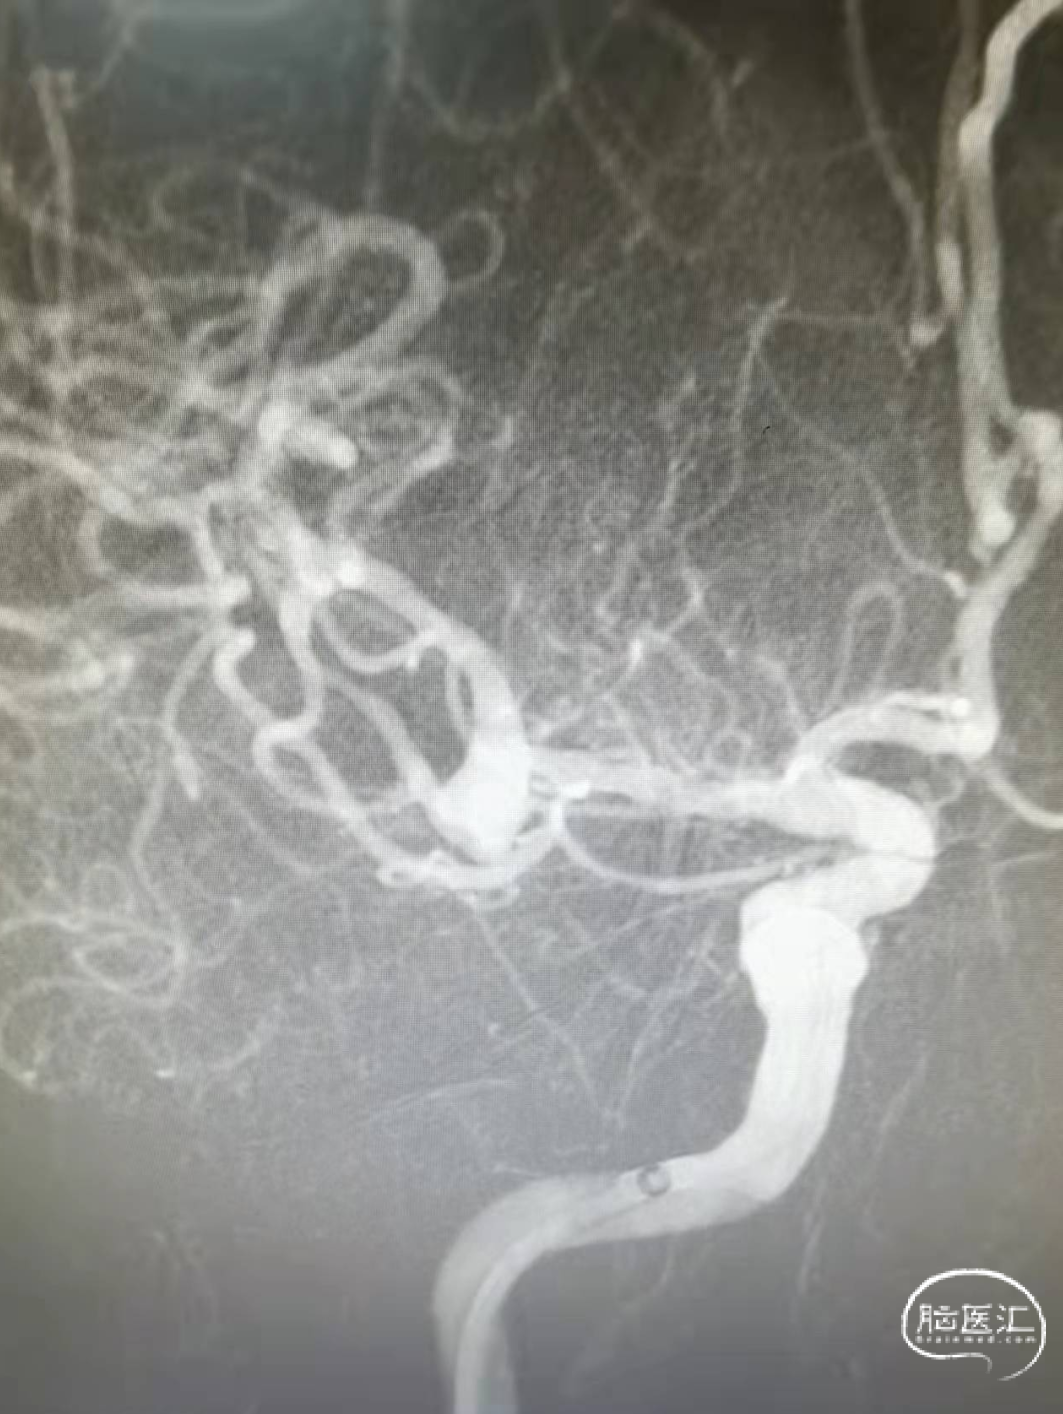

术前影像

术前3D:动脉瘤大小约2.52*2.34mm,颈宽约2.38mm,载瘤动脉近端约3.63mm,远端4.08mm。

术后造影

术后造影(如下动态影像)。